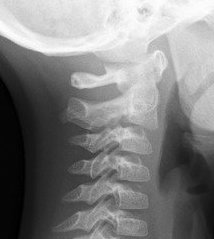

Relative translation of (typically) C2 on C3

- Physiological variant in children up to 8

Subluxation of up to 4 mm

- C2/3 in 40% children

- C3/4 14%

Reduces with extension

Diagnosis

1. Swischuk's Line

- drawn along spinolaminar line C1 & C3

- C2 should be within 1.5 - 2mm of this line

2. Pseudosubluxation will reduce with extension